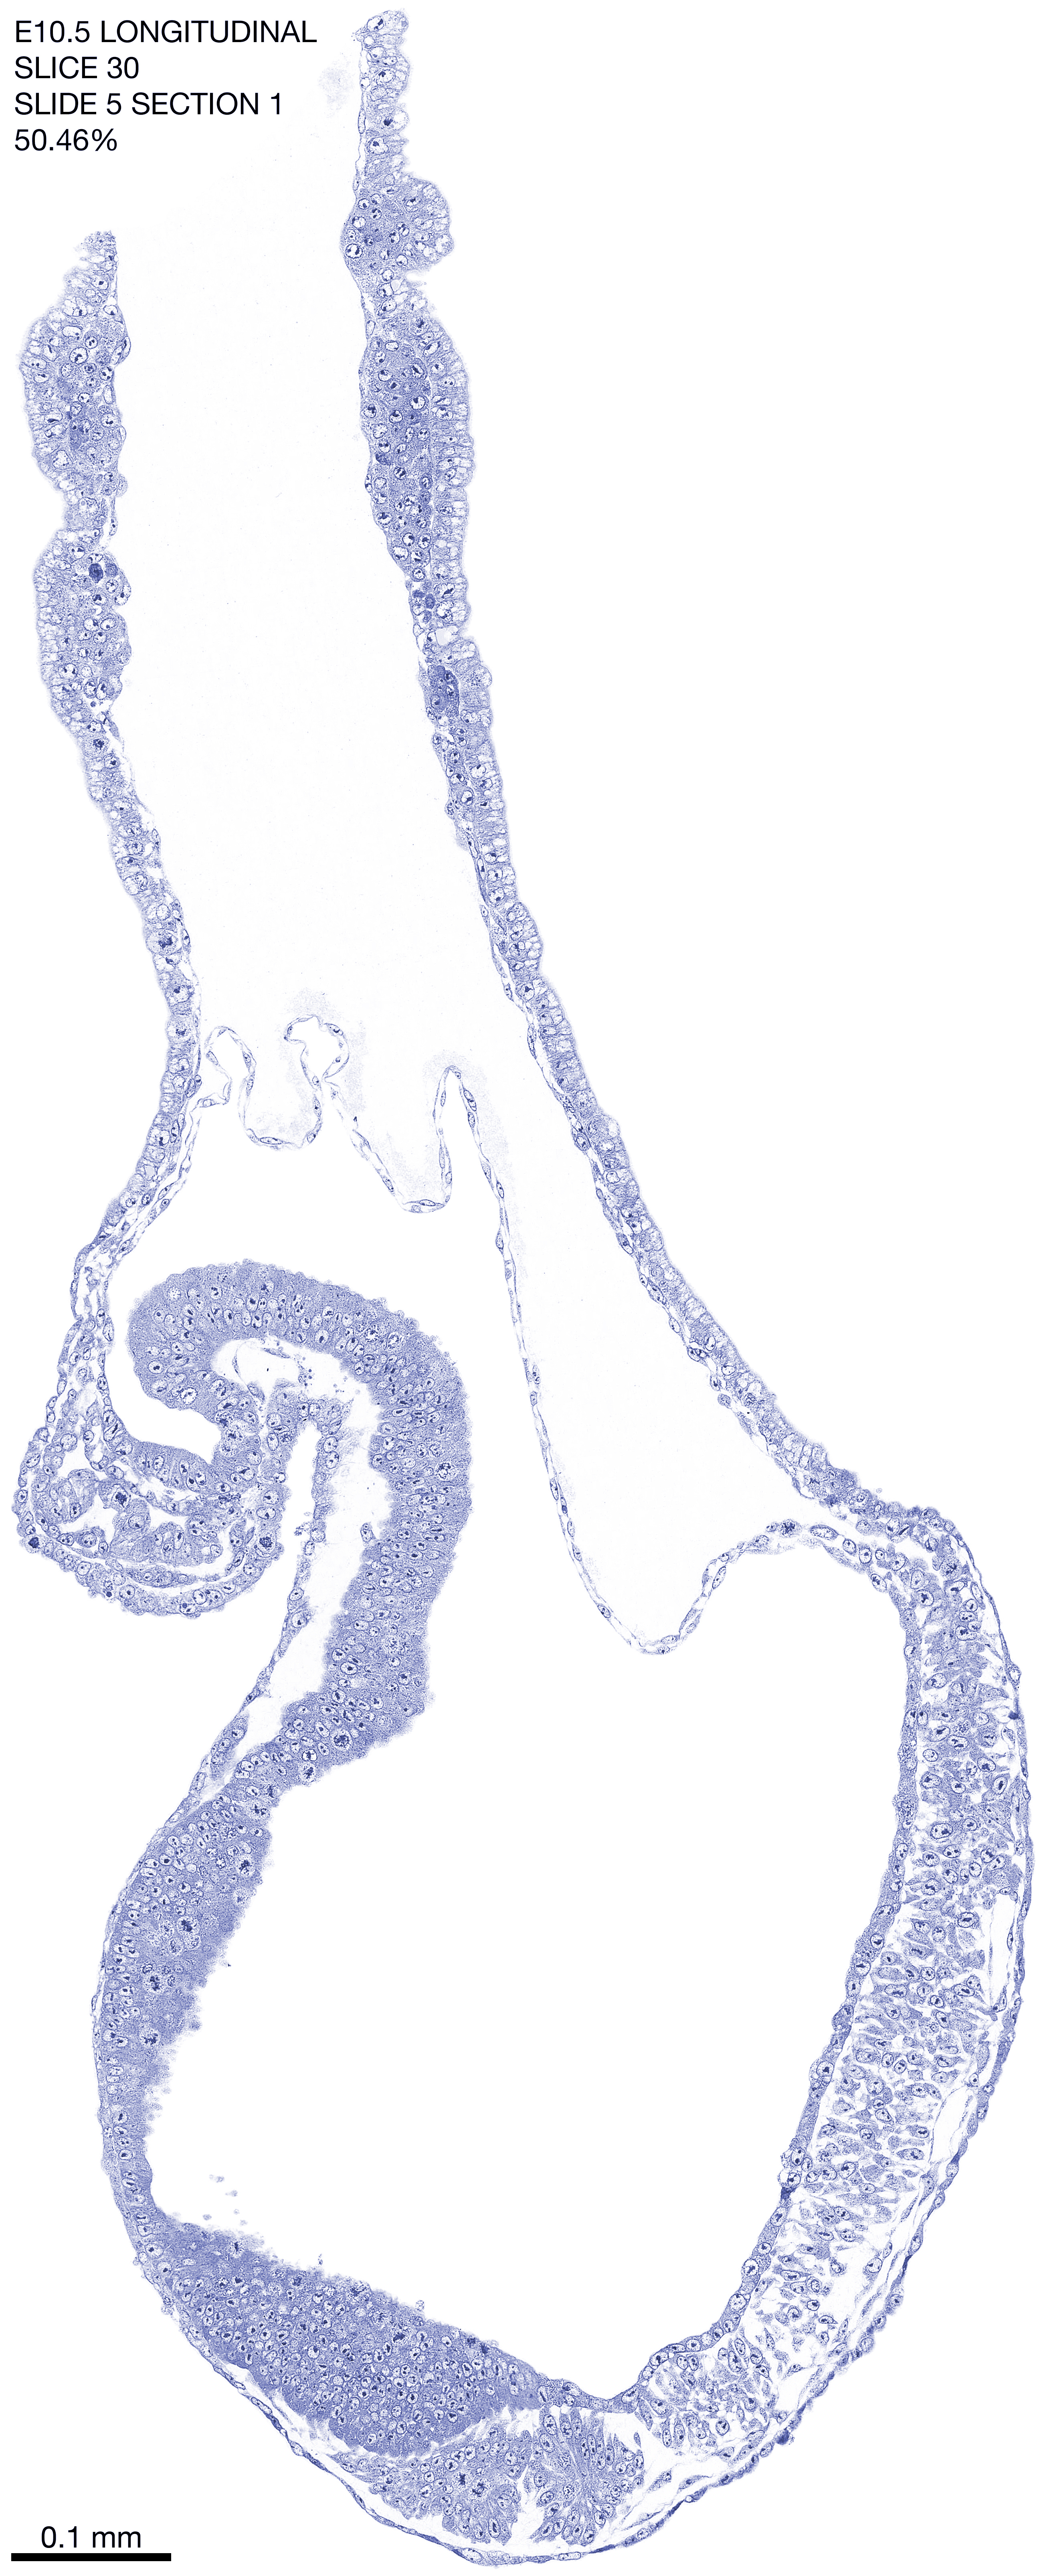

E10.5 Longitudianal Archive This page contains jpg files of ALL SLICES (each 3µm thick) that were scanned of the E10.5 longitudinally cut specimen. Download: Large | High Res Download: Large | High Res Download: Large | High Res Download: Large | High Res Download: Large | High Res Download: Large | High Res Download: Large | High Res Download: Large | High Res Download: Large | High Res Download: Large | High Res Download: Large | High Res Download: Large | High Res Download: Large | High Res Download: Large | High Res Download: Large | High Res Download: Large | High Res Download: Large | High Res Download: Large | High Res Download: Large | High Res Download: Large | High Res Download: Large | High Res Download: Large | High Res Download: Large | High Res Download: Large | High Res Download: Large | High Res Download: Large | High Res Download: Large | High Res Download: Large | High Res Download: Large | High Res Download: Large | High Res Download: Large | High Res Download: Large | High Res Download: Large | High Res Download: Large | High Res Download: Large | High Res Download: Large | High Res Download: Large | High Res Download: Large | High Res Download: Large | High Res Download: Large | High Res Download: Large | High Res Download: Large | High Res Download: Large | High Res Download: Large | High Res Download: Large | High Res Download: Large | High Res Download: Large | High Res Download: Large | High Res Download: Large | High Res Download: Large | High Res Download: Large | High Res Download: Large | High Res Download: Large | High Res Download: Large | High Res Download: Large | High Res Download: Large | High Res Download: Large | High Res Download: Large | High Res